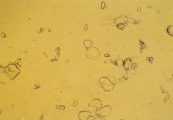

КАЛЬЦИЙ ОКСАЛАТНАЯ КРИСТАЛЛУРИЯ

Особенности

Кристаллы

кальция оксалата дегидрата обычно

бесцветные, характерной октоэдрической

или овальной формы (рис. 4-11). Под световым

микроскопом выглядят как большие или

маленькие квадраты, углы которых

соединены диагональными линиями.

Кристаллы кальция оксалата обнаруживаются

в кислой, нейтральной или щелочной

моче.Кристаллы кальция оксалата

моногидрата различаются по размерам и

могут быть в форме веретена, овальными

(как конопляное семечко) или в форме

гантели (рис.12). Кристаллы кальция

оксалата моногидрата были обнаружены

у собак с закисленной мочой, особенно

у животных с отравлениями этиленгликолем

(рис. 13-17). Они растворимы в соляной

кислоте, но не растворимы в уксусной

кислоте. Кристаллы могут встречаться

в комбинации с кальций оксалат дегидратами

и другими типами кристаллов.

Интерпретация

Кристаллы кальция оксалата дегидрата

могут встречаться, по-видимому, у здоровых

собак и кошек, а также у собак и кошек с

уролитами, состоящими преимущественно

из кальция оксалата. Хотя они могут быть

обнаружены у собак с отравлениями

этиленгликолем, подобные кристаллы

менее типичны, чем кристаллы кальция

оксалата моногидрата (отравление

этиленгликолем может также протекать

без кристаллурии).

Кристаллы кальция

оксалата моногидрата могут встречаться

одни или в комбинации с кальций оксалат

дегидратом или другими типами кристаллов.

Большие количества кристаллов кальций

оксалат моногидрата (или дегидрата) в

свежем образце мочи свидетельствуют о

гиперкальциевых или гипероксалатных

расстройствах (как например, отравление

этиленгликолем), особенно если они

встречаются в виде агрегаций или растут

до больших размеров.